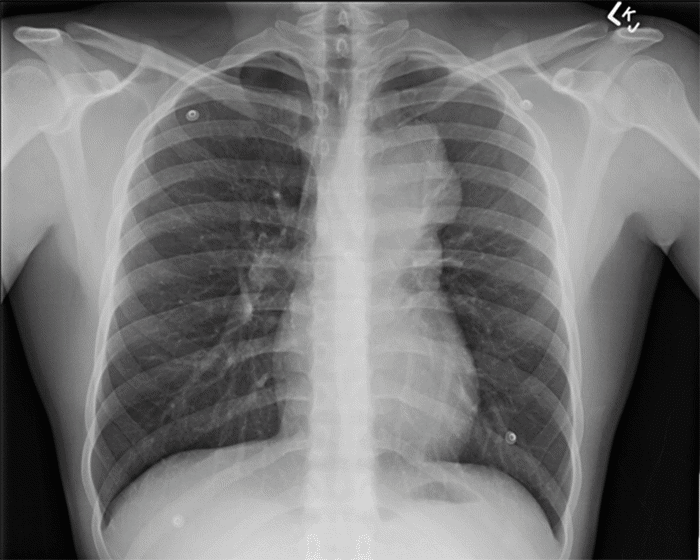

A 20-year-old male presented with dyspnea and chest pain that radiated to the left shoulder and back. He denied fever, cough, nausea, vomiting, night sweats, or weight loss and reported no tobacco or environmental exposures. Laboratory values were all within normal limits apart from an elevated alkaline phosphatase (172 IU/L, normal: 20-140 IU/L). Alpha-fetoprotein marker was found to be 1.20 ng/mL (normal: <10 ng/mL), lactate dehydrogenase (LDH) was found to be 142 U/L (normal: 140-280), and beta-human chorionic gonadotropin (ß-hCG) was negative. Plain radiograph (Figure 1) was significant for a left paratracheal lobulated mediastinal mass causing right tracheal deviation. Chest computed tomography (CT) revealed a large anterior mediastinal mass measuring 8.5 × 8.3 × 7.2 cm (Figure 2 and Figure 3). Scrotal ultrasound revealed no masses, though nonspecific scattered bilateral testicular microcalcifications were noted. A CT-guided biopsy of the mass was performed however was non-diagnostic. Due to a high index of suspicion for malignancy, an incisional biopsy via Chamberlain procedure was performed.

Figure 1. Chest X ray Image with Left Paratracheal Lobulated Mediastinal Mass Causing Rightward Tracheal Deviation. Published with Permission